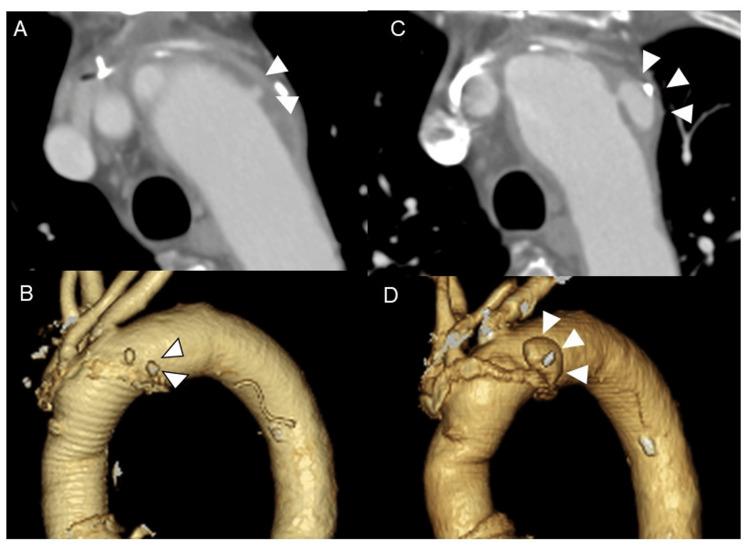

Ulcer-like projections (ULPs) with a tendency to enlarge are at risk of aortic events such as new dissection, aneurysmal formation, or rupture and require therapeutic intervention. However, what should be done after open chest surgery when standard thoracic endovascular aortic repair (TEVAR) cannot be performed is debatable. Here, we present a case of coil embolization of a newly enlarged ULP that was not amenable to TEVAR following a hemiarch aortic arch repair. A 68-year-old male with a history of ascending and hemiaortic arch repair for acute type A aortic dissection presented with a chief complaint of chest pain three months prior to presentation. A post-type A dissection ULP remained in the aortic arch but had enlarged over the three months. Therapeutic intervention was planned to avoid aortic events; however, standard and fenestrated TEVAR were going to be anatomically challenging. Since the patient was in poor general condition after diverticulitis and stroke, reopened total arch replacement and total debranching TEVAR were avoided. The neck of the ULP was narrow and had a small volume; therefore, we assessed that the coil-packing method could embolize the ULP. Coil embolization was successful, and the patient had no postoperative complications. A computed tomography scan at the remote stage showed no recanalization or enlargement, and the patient was stable. Coil embolization may be attempted for arch ULP that can enlarge if the ULP can be embolized with intra-aneurysmal packing when it is difficult to perform a reopen surgery or TEVAR, including standard zone II, total debranching, and fenestrated TEVAR.

具有扩大倾向的溃疡样突出(ULP)有发生主动脉事件的风险,如新发夹层、动脉瘤形成或破裂,需要进行治疗干预。然而,在开胸手术后无法进行标准胸主动脉腔内修复术(TEVAR)时应采取何种措施仍存在争议。在此,我们报告一例在半弓主动脉弓修复术后,对一个新增大的、无法进行TEVAR的ULP进行弹簧圈栓塞的病例。一名68岁男性,有因急性A型主动脉夹层进行升主动脉和半弓主动脉弓修复的病史,在就诊前三个月因胸痛为主诉前来就诊。A型夹层后残留的ULP位于主动脉弓,但在三个月内有所增大。计划进行治疗干预以避免主动脉事件;然而,标准和开窗TEVAR在解剖学上具有挑战性。由于患者在患憩室炎和中风后全身状况较差,避免了再次进行全弓置换和全去分支TEVAR。ULP的颈部狭窄且体积小;因此,我们评估弹簧圈填充法可栓塞ULP。弹簧圈栓塞成功,患者术后无并发症。远期计算机断层扫描显示无再通或增大,患者情况稳定。对于难以进行再次手术或TEVAR(包括标准II区、全去分支和开窗TEVAR)的、如果ULP可通过瘤内填充进行栓塞且可能增大的弓部ULP,可尝试弹簧圈栓塞。